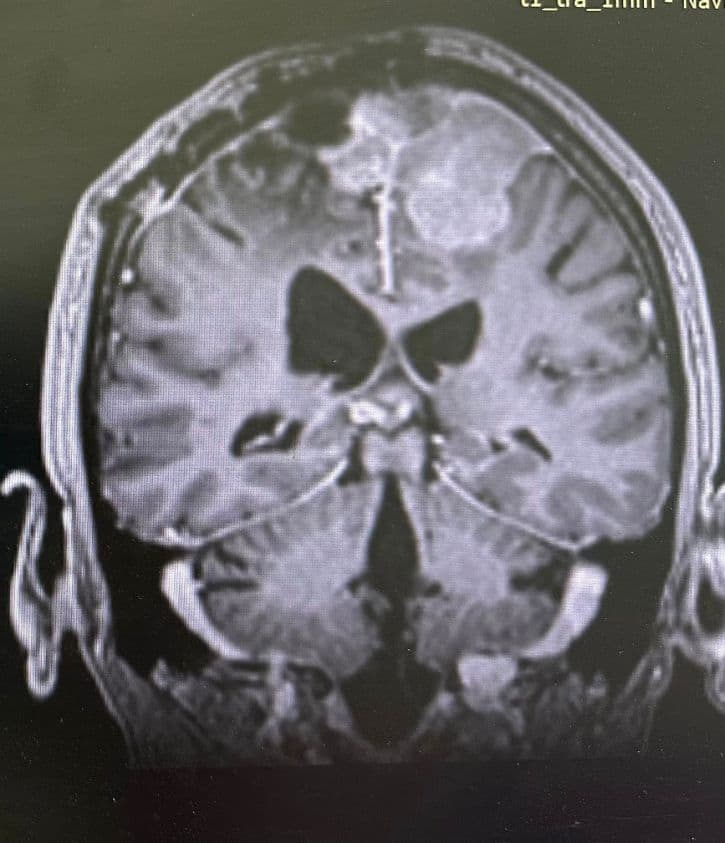

Presurgical Embolization of Brain Meningiomas reduces intraoperative hemorrhagic events and fascilitates surgical excision (Professor of Neurosurgery and Endovascular Neurosurgery V. Panagiotopoulos & Professor of Interventional Neuroradiology P. Zampakis).